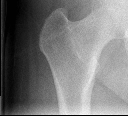

胫腓骨上段粉碎性骨折1(14.68MB)

胫腓骨上段粉碎性骨折2(10.09MB)

胫腓骨上段粉碎性骨折1

胫腓骨上段粉碎性骨折2